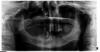

Doc Опубликовано 17 июля, 2013 Поделиться Опубликовано 17 июля, 2013 Мне 50 лет. Зубов практически не осталось.Причем, зубы не удалялись, а "ушли" сами.Врач предлагает удалять остатки и за одну операцию делать синуслифтинг с двух сторон и ставить 8 имплантов сверху и 8 снизу с последующей(через 2-4 месяца) установкой несъемных протезов. Мероприятие, как понимаете, очень дорогостоящее... да и травматичное. Не могу решиться. Специалисты, пожалуйста, выскажите свое мнение, реально ли это? Или в моей ситуации это пустая трата сил, денег, нервов. Заранее благодарен.По одной ортопантомограмме диагноз не ставят, но похоже, что все правда. Удалять все придется, как ни крути. Количество сверху и снизу может меняться, имплантолог должен видеть КТ, чтобы сказать точнее сколько и куда поставить имплантатов.Что касается затрат, то все зависит от конкретной задачи. Если Вам без разницы что носить, то можно и съемные протезы в стаканчике на тумбочке держать по ночам. Быстро и дешево. Если хочется качества жизни, то безусловно в Вашем случае поможет только имплантация. Но долго и дорого. Вам виднее, выбирайте. 3 Ссылка на комментарий